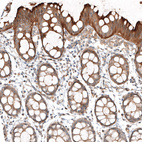

Immunohistochemical staining of human prostate shows moderate membranous and cytoplasmic positivity in smooth muscle cells and glandular cells.